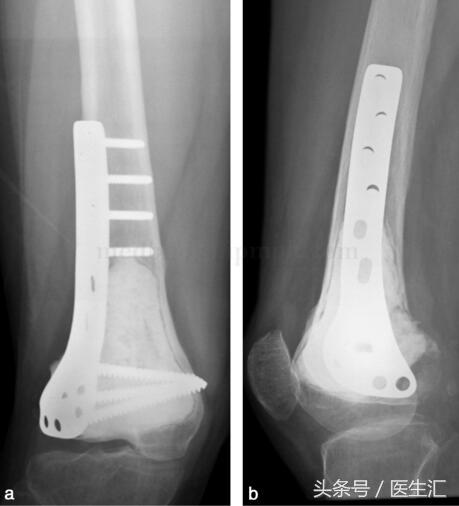

由于行軟骨下骨處植骨,故囑患者術(shù)后3個(gè)月,攝片示植骨愈合后,患肢開始負(fù)重(圖29‐4a,圖29‐4b)。此患者已術(shù)后隨訪兩年,局部無(wú)復(fù)發(fā),胸部無(wú)轉(zhuǎn)移,植骨已愈合,功能良好。

圖29‐4

a﹒術(shù)后X 線正位片;b﹒術(shù)后X 線側(cè)位片